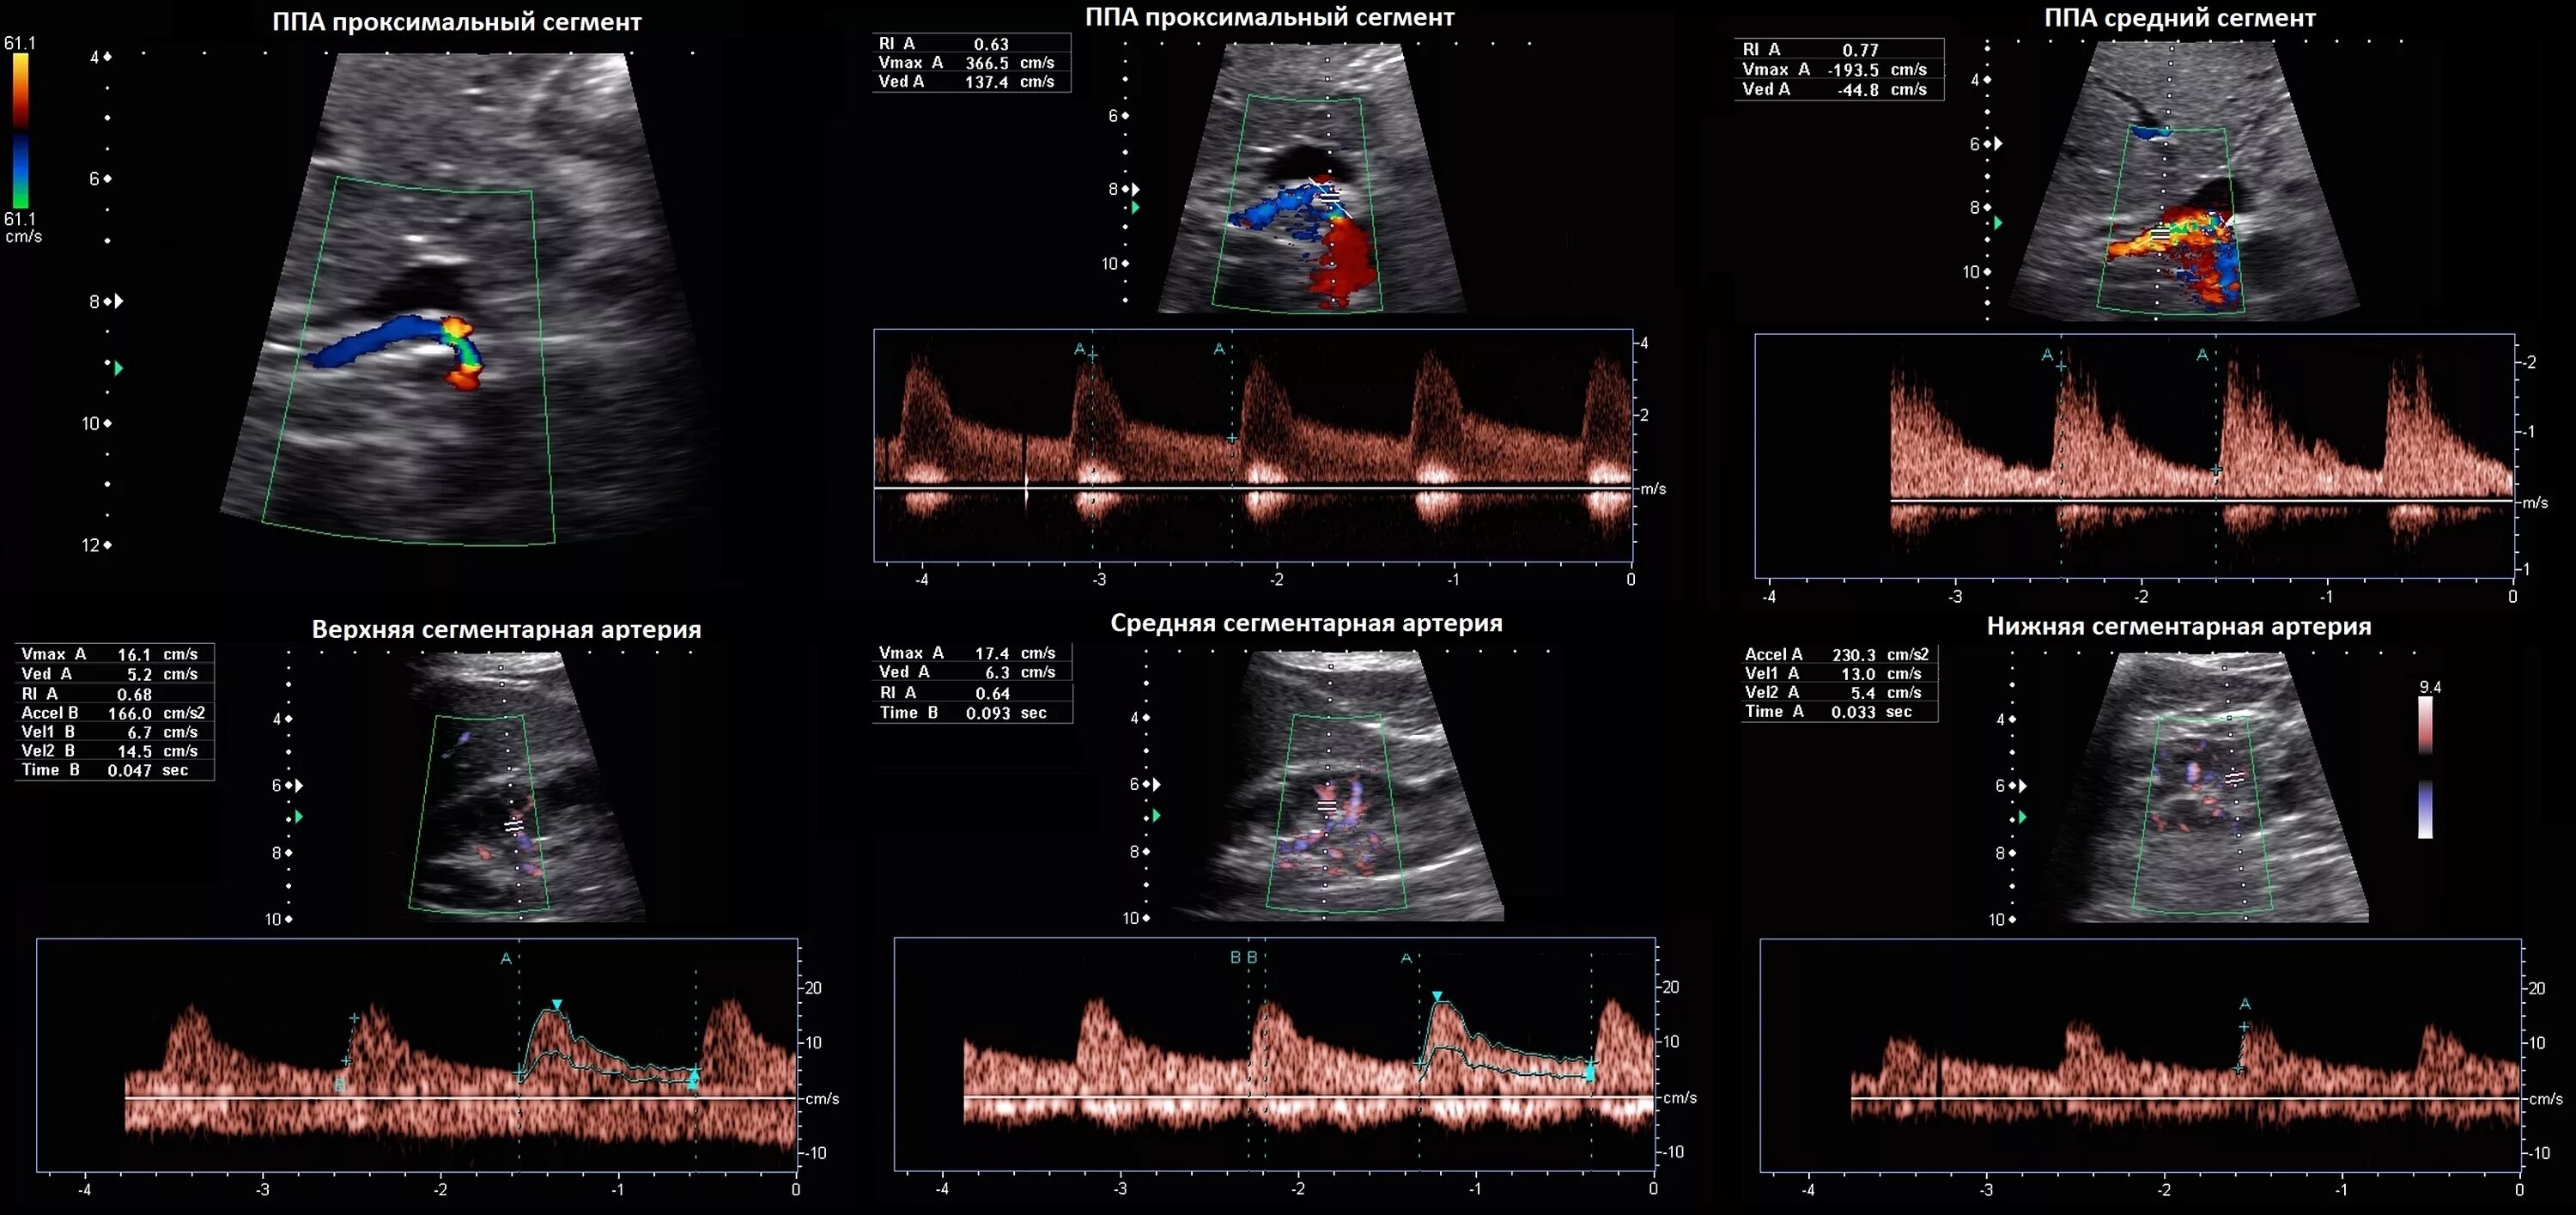

Тип кровотока 1 типа